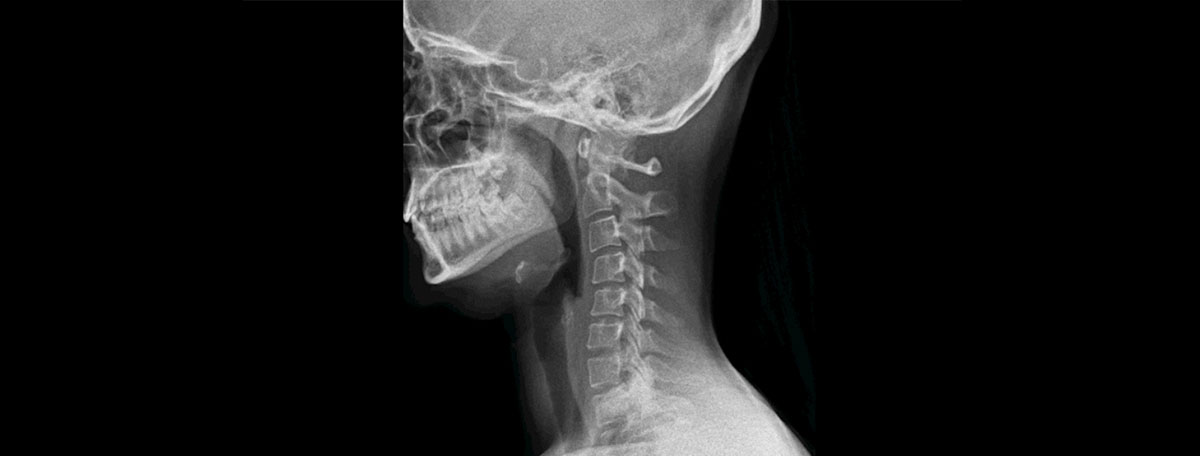

La radiocirugía, a pesar de que su nombre puede llevar a confusión, es una técnica externa en la que no es necesario realizar incisiones en el paciente. En este procedimiento, se aplican grandes dosis de radiación de forma precisa sobre los tumores para destruir las células cancerosas. Esta técnica permite reducir el número de sesiones, por lo que se minimizan los efectos dañinos en el tejido sano.

- Radiocirugía estereotáctica (SRS): los haces de radiación de alta potencia se enfocan de forma muy precisa en una zona específica, normalmente, en el cerebro, el cuello, los pulmones, el hígado o la columna vertebral.

El primer uso de la radiocirugía fue para tratar tumores cerebrales, pero, con el paso del tiempo, se han desarrollado aplicaciones para otro tipo de patologías como malformaciones en las venas o las arterias, la neuralgia del trigémino, los tumores benignos ubicados en el sistema auditivo o cáncer en la hipófisis, los pulmones, el hígado, los ojos, la próstata o la columna vertebral.